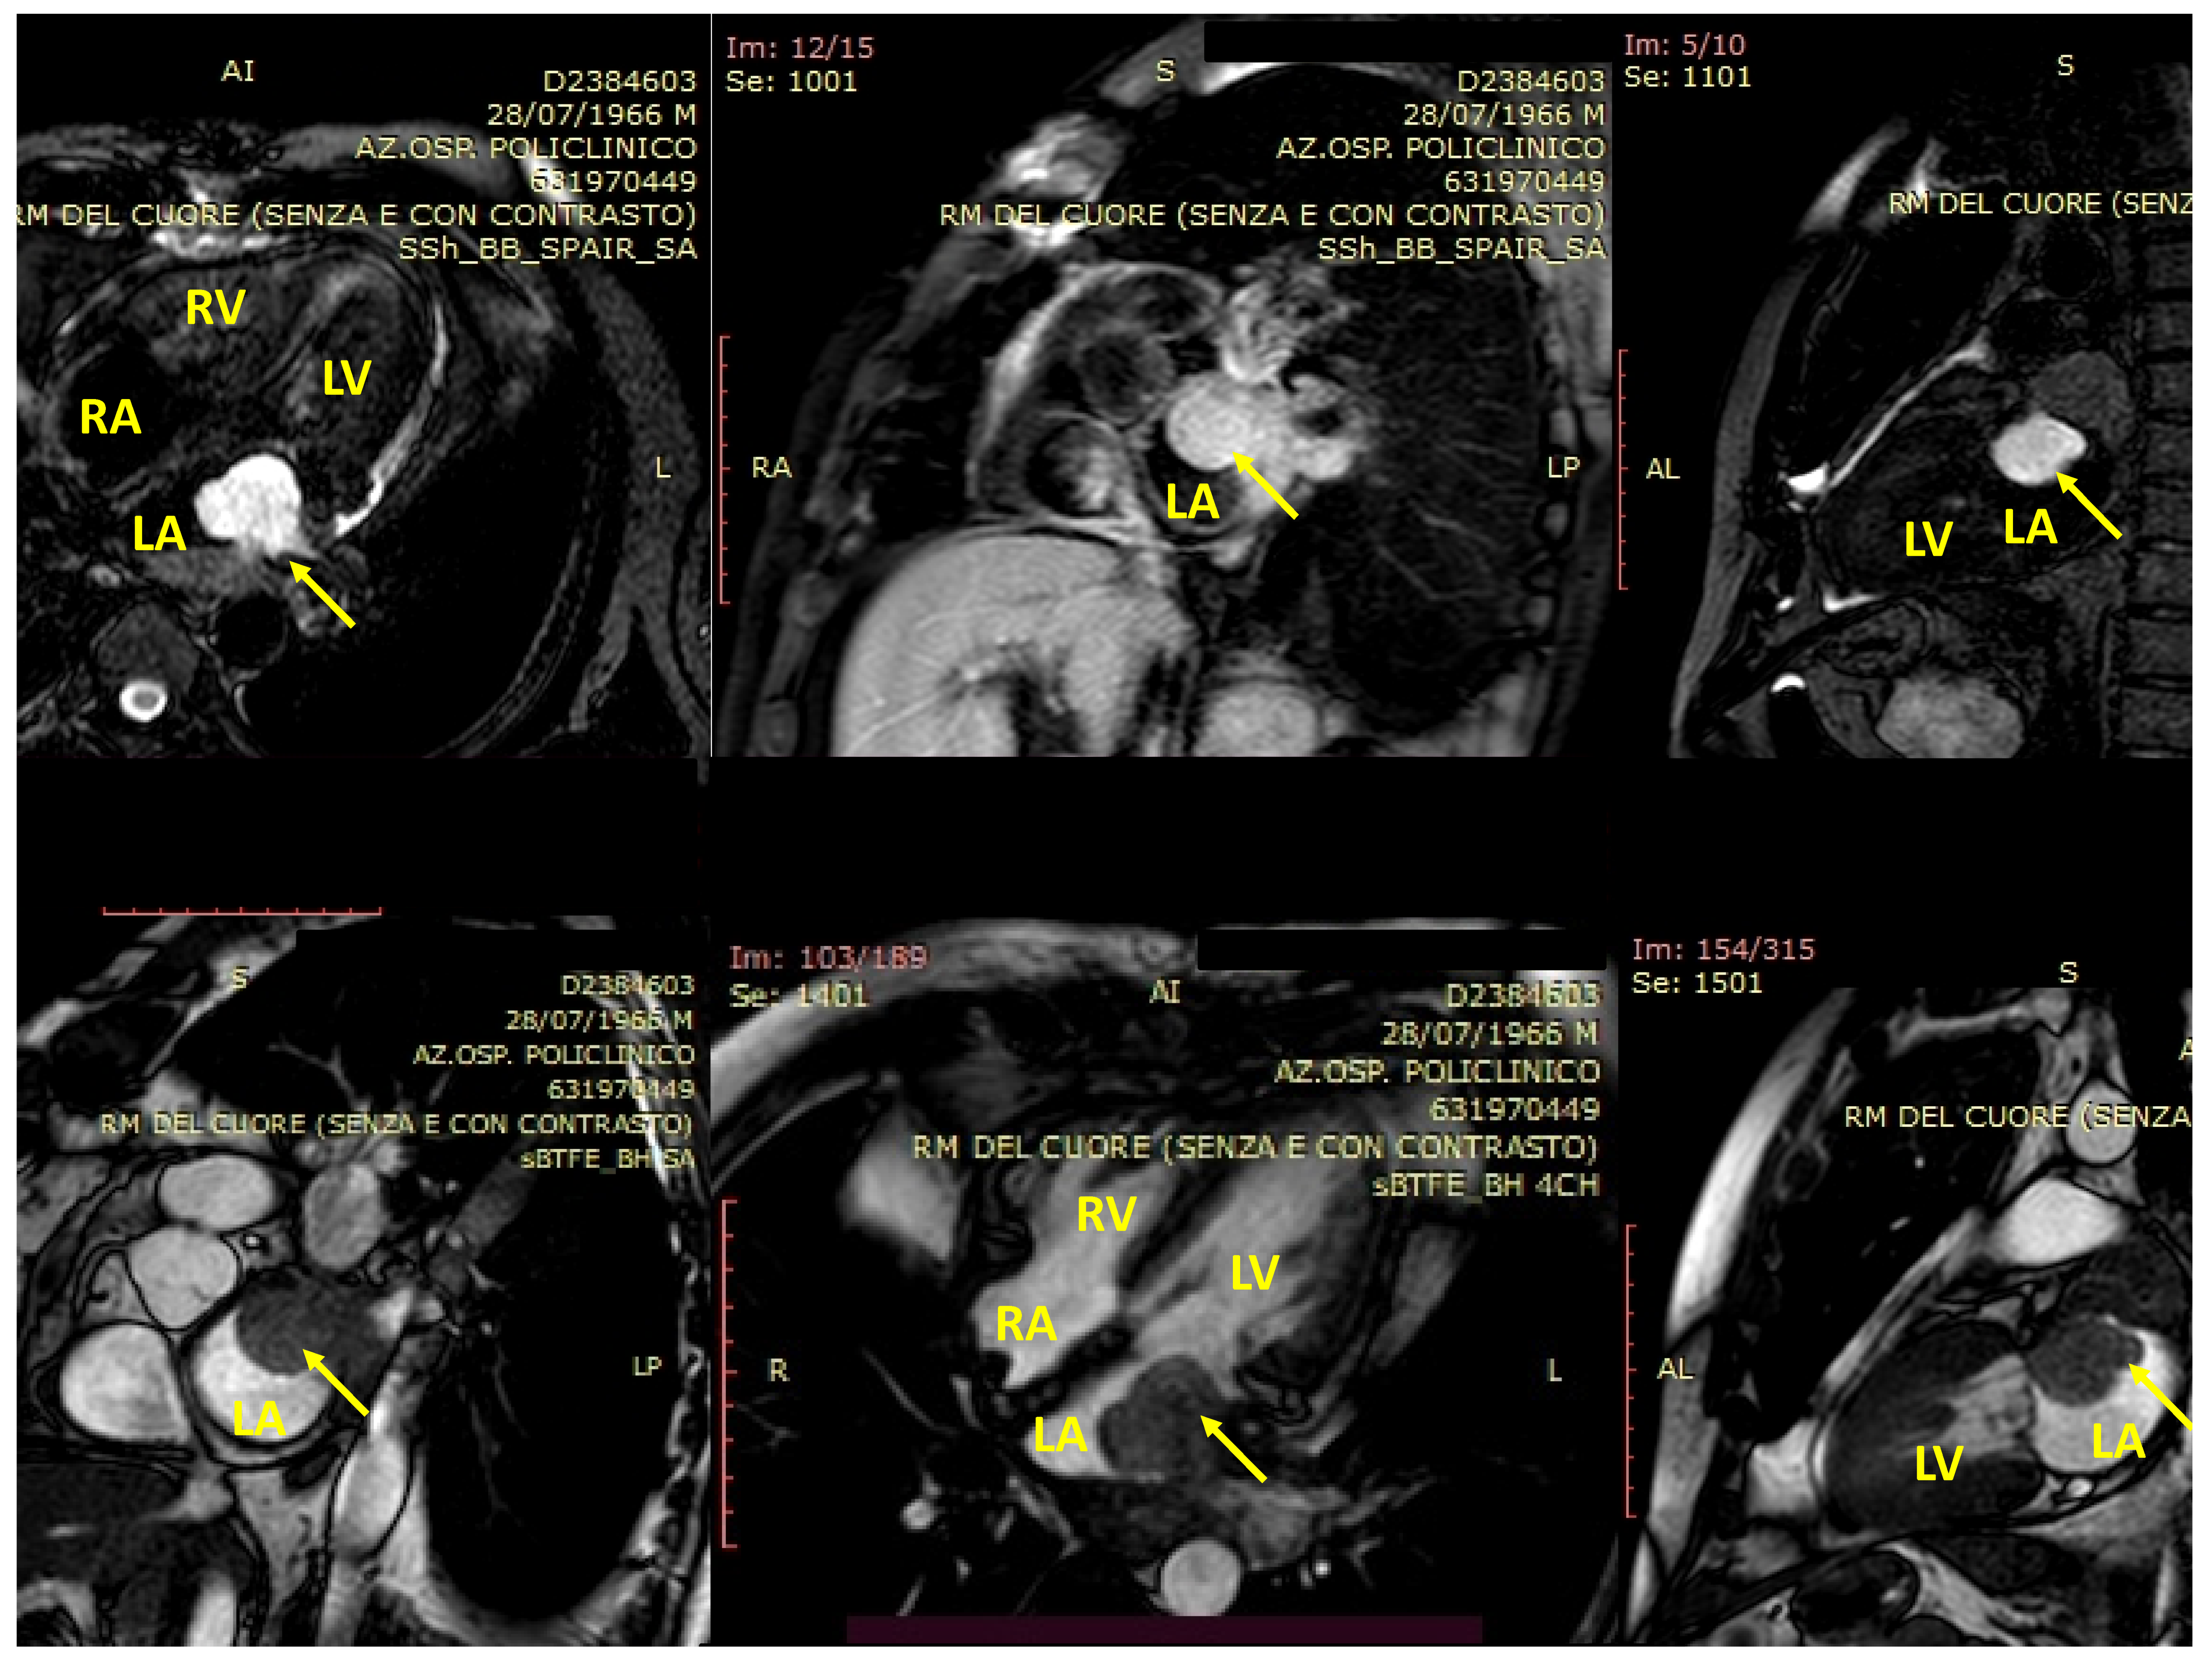

4. cMRI in pSTS-h

- Hoey, E.T.; Shahid, M.; Ganeshan, A.; Baijal, S.; Simpson, H.; Watkin, R.W. MRI assessment of cardiac tumours: Part 1, multiparametric imaging protocols and spectrum of appearances of histologically benign lesions. Quant. Imaging Med. Surg. 2014, 4, 478–488. [Google Scholar] [CrossRef]

- Hoey, E.T.; Shahid, M.; Ganeshan, A.; Baijal, S.; Simpson, H.; Watkin, R.W. MRI assessment of cardiac tumours: Part 2, spectrum of appearances of histologically malignant lesions and tumour mimics. Quant. Imaging Med. Surg. 2014, 4, 489–497. [Google Scholar] [CrossRef]

- Mousavi, N.; Cheezum, M.K.; Aghayev, A.; Padera, R.; Vita, T.; Steigner, M.; Hulten, E.; Bittencourt, M.S.; Dorbala, S.; Di Carli, M.F.; et al. Assessment of Cardiac Masses by Cardiac Magnetic Resonance Imaging: Histological Correlation and Clinical Outcomes. J. Am. Hear. Assoc. 2019, 8, e007829. [Google Scholar] [CrossRef]